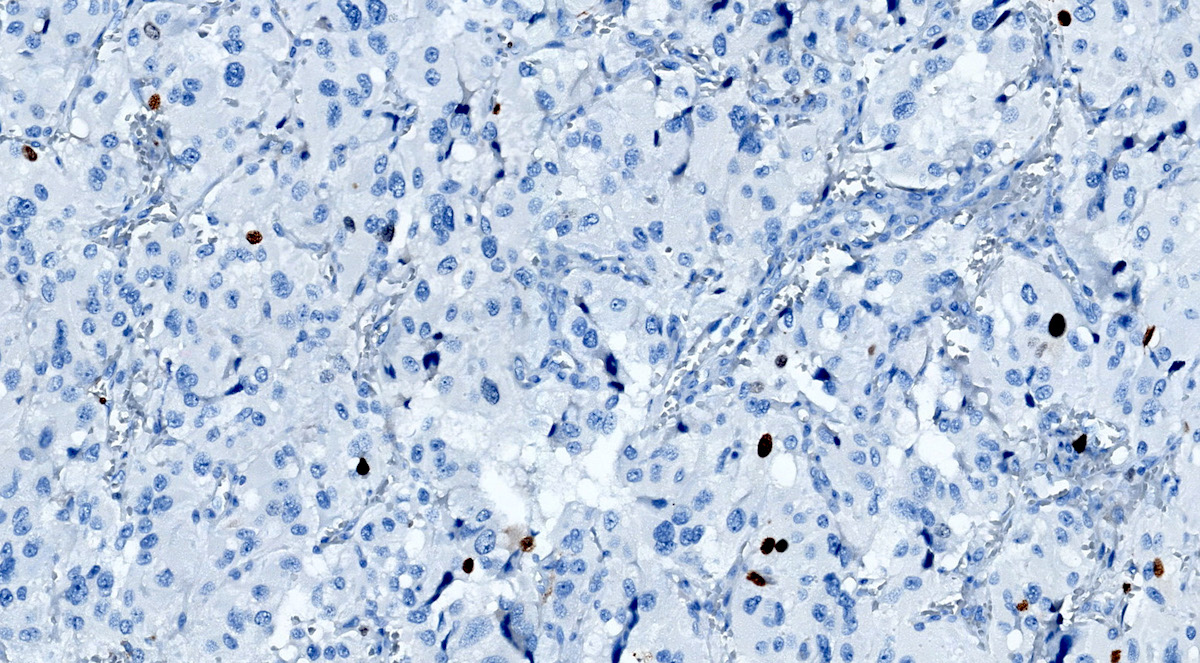

Microscopic (histologic) images

Contributed by Luvy Delfin, M.D. and Sylvia L. Asa, M.D., Ph.D.

Positive stains

- INSM1 (diffuse nuclear) (Am J Surg Pathol 2018;42:665)

- Chromogranin A (can be only focal or perinuclear dot-like golgi pattern)

- Synaptophysin (Histol Histopathol 1993;8:429)

- CD56 (Endocr Pathol 2002;13:149)

- S100 may be diffusely positive (J BUON 2018;23:1540)

- GATA3 (diffuse nuclear) (Hum Pathol 2020;103:72, Am J Surg Pathol 2014;38:13, J Clin Med 2018;7:280)

- Tyrosine hydroxylase (critical enzyme required for catecholamine synthesis; usually diffuse and strong in sympathetic paragangliomas, may be weak or focal in parasympathetic tumors) (Hum Pathol 2020;103:72)

- Dopamine beta hydroxylase and phenylethanolamine N methyltransferase (PNMT) (epinephrine producing tumors) (see Diagram below) (Neuroendocrinology 2015;101:289, J Clin Med 2018;7:280)

- Sustentacular cells: S100, GFAP and SOX10 (Hum Pathol 2020;103:72)

- Ectopic immunoexpression of hormones: serotonin, ACTH, CRH, VIP, leu enkephalin substance P, gastrin, somatostatin, vasopressin, MSH and calcitonin (Arch Endocrinol Metab 2017;61:291, J Clin Endocrinol Metab 2021;106:598, Endocr Pract 2014;20:e145, Ann Intern Med 1979;91:208)

- IHC surrogate markers for germline mutations:

- SDHB or SDHA expression loss: germline SDHx mutations (Lancet Oncol 2009;10:764)

- FH expression loss: germline FH mutation (HLRCC) (Hum Pathol 2018;71:47)

- Carbonic anhydrase IX (CAIX) expression: 80% of VHL mutation (Mod Pathol 2020;33:57)

- Inhibin alpha: any hypoxic pathway disease (SDHx, VHL, etc.) (Am J Surg Pathol 2021;45:1264)

- Reticulin highlights the nesting pattern (Int J Gynecol Pathol 1991;10:203, Exp Toxicol Pathol 2013;65:631)

Contributed by Luvy Delfin, M.D. and Sylvia L. Asa, M.D., Ph.D.